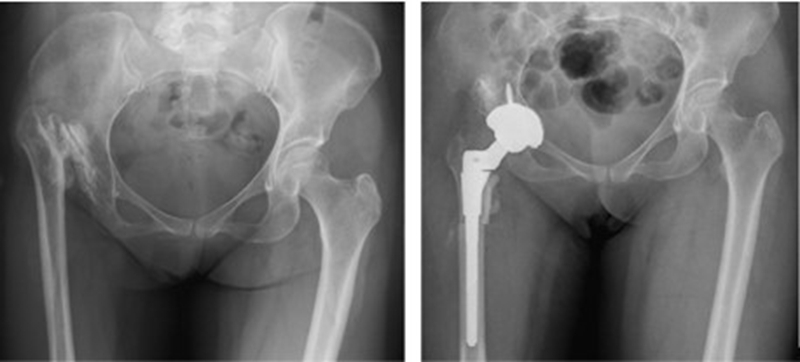

Ⅱ、股骨颈畸形---髋内外翻,offset异常

(1)颈干角偏小(<120°)——髋内翻

髋内翻,颈干角小,偏心距较大,选择high-Offset假体,以维持外展肌张力。

(2)颈干角过大(>140°) ——髋外翻

髋外翻多见于DDH,难度在于股骨距内侧皮质阻挡假体完全坐入髓腔,强行打击造成股骨距骨折。